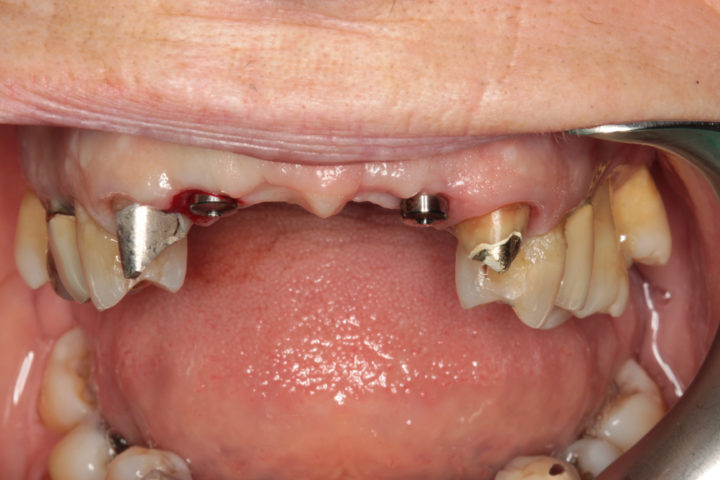

Riabilitazione di un vecchio ponte

Rimozione del ponte esistente con monconi cariati, esecuzione di estrazioni dentarie mirate, rigenerazione ossea guidata, e completamento del trattamento con un ponte in ceramica supportato da impianti in titanio.